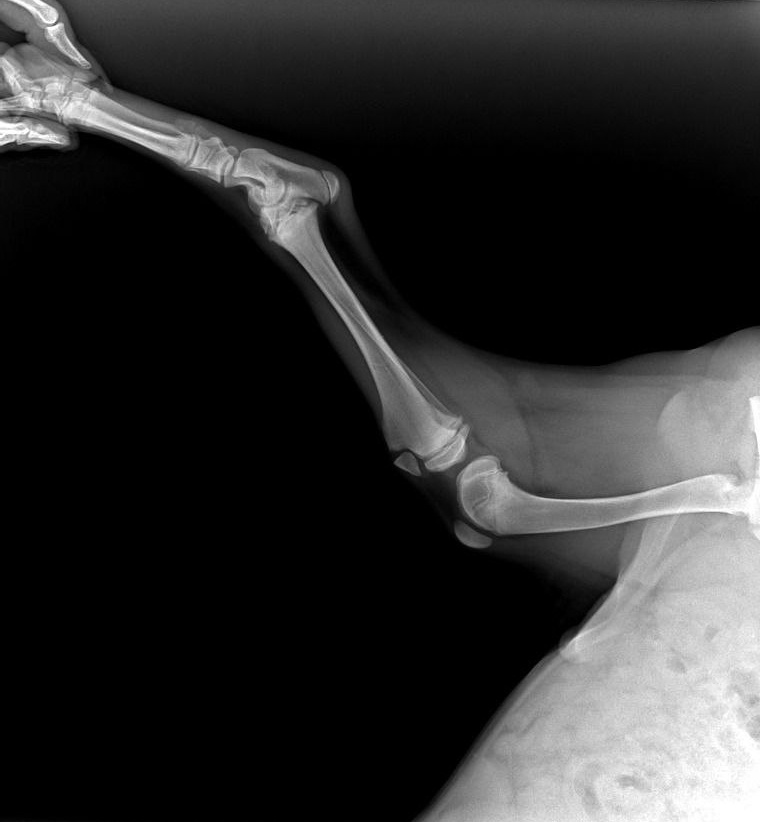

К нашему огромному облегчению и счастью, Цой оказался настоящим счастливчиком! Он чудом избежал серьезных травм, отделавшись ссадинами, гемaтомами и, конечно, сильным испугом. Мы сразу же сделали рентген задней лапки, на которую он хромал, и выдохнули — переломов нет, только сильный ушиб!